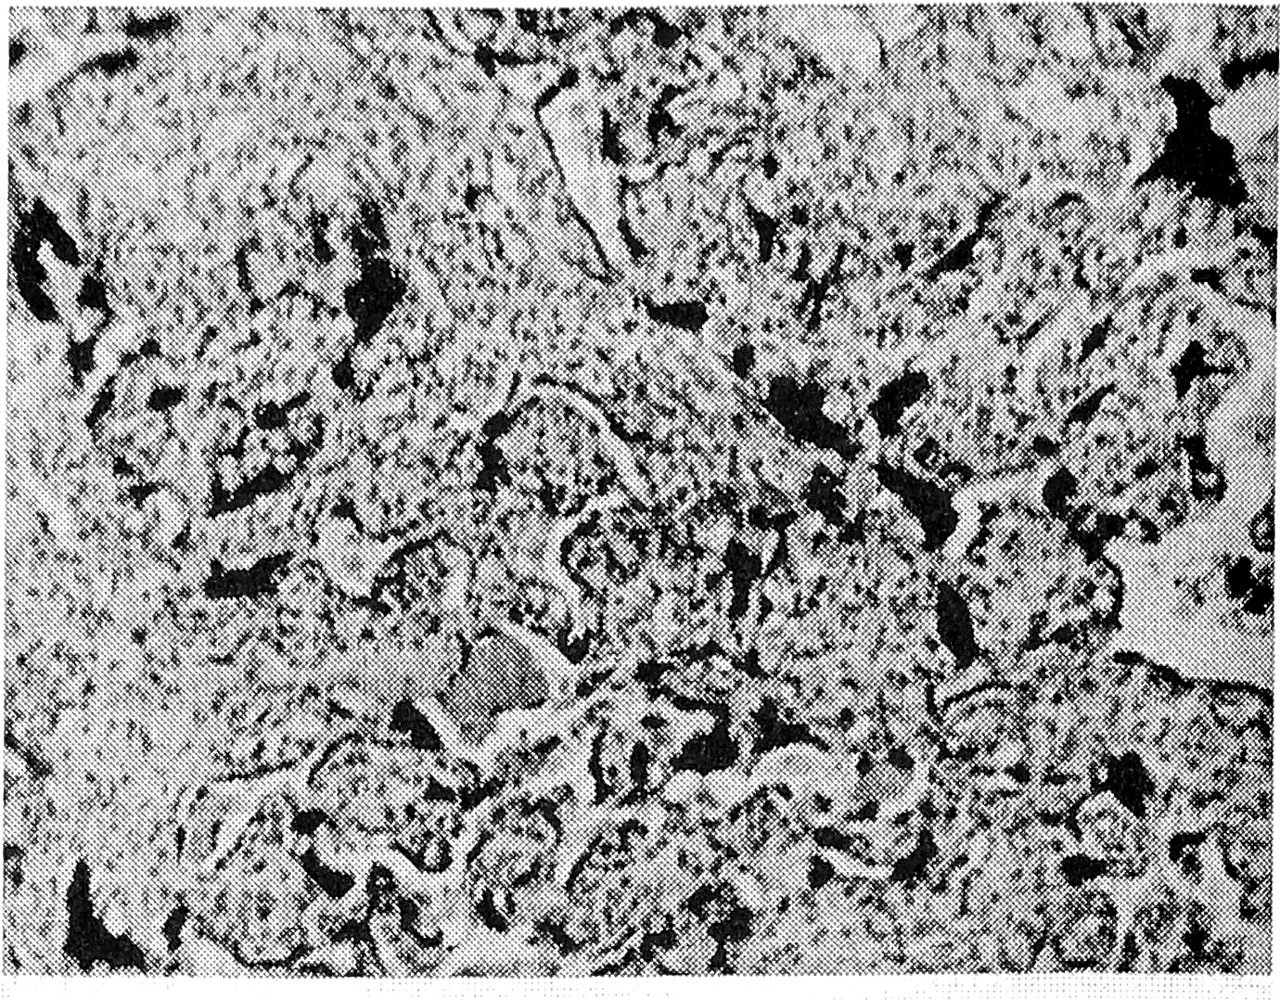

У тех женщин 1-й группы, у которых в качестве возбудителя была идентифицирована уреаплазма, отсутствовали тяжелые формы базального децидуита и относительно низкой была частота отечного синдрома (не более чем в 30% случаев). В то же время отмечалось появление в подавляющем большинстве случаев артериосклероза в средних ворсинах (рис. 3) с присоединением в отдельных плацентах продуктивного виллузи- та и продуктивного васкулита в опорных ворсинах. В половине наблюдений была установлена выраженная гиперемия в сосудах терминальных ворсин с бедным содержанием синцитиальных почек на их поверхности, у остальных — гиперпластический тип терминальных ворсин (строма богата клеточными элементами) с недостаточной их васкуляризацией, но с компенсаторным увеличением числа синцитиальных почек. В большей части случаев в плаценте имели место мелкие и редкие кальцификаты. Создается впечатление, что при инфицировании уреаплазмой доминируют сосудистая патология плаценты и стромальная реакция ворсин. Своеобразие хламидийной инфекции заключалось в том, что вне зависимости от степени лимфоцитарной инфильтрации decidua basalis (от легкой до умеренной) к отечному синдрому, частота которого достигала почти 100%, в половине случаев присоединялись кровоизлияния и крупные петрификаты в базальной пластинке. Одновременно известковые отложения имели место и в ворсинах парабазальной зоны (рис. 4). Наиболее ярким и постоянным признаком была выраженная гиперемия ворсин, иногда с явлениями стаза в парабазальной зоне; в 2 случаях выявлен ангиоматоз ворсин (рис. 5). В трети наблюдений обнаружены значительные фибриноидные отложения в базальной пластинке, межворсинчатом пространстве или на поверхности ворсин (чаще в субхориальной зоне), что в 3 случаях осложнилось развитием крупных очагов белых инфарктов. Атрофические и дистрофические изменения синцитиотрофобласта на поверхности терминальных ворсин в 50% наблюдений сочетались с умеренной гиперплазией синцитиальных почек. Обращали на себя внимание вакуольная дистрофия цитотрофобласта, отек амниона в плодных экстраплацентарных оболочках и гладком хорионе.

Рис. 4. Петрификаты в базальной пластинке и парабазальной зоне при хламидиозе, х 100.